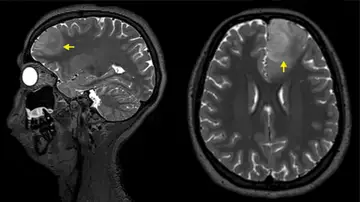

"Podemos observar que las partículas de tinta se acumulan en los ganglios linfáticos y sospechamos que el cuerpo las percibe como sustancias extrañas", explica el hematólogo de la Universidad de Odense Henrik Frederiksen. "Esto puede significar que el sistema inmunológico está constantemente tratando de responder a la tinta, y aún no sabemos si esta tensión persistente podría debilitar la función de los ganglios linfáticos o tener otras consecuencias para la salud".